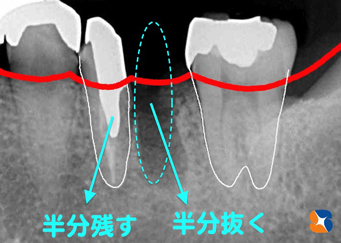

下記の写真(治療完成)も、右から2番目の奥歯を半分抜いて(水色2)、半分残した(水色1)症例です。

〈3連結の構成説明=下記写真〉

水色1:右から2番目の奥歯を半分残して左端を支える

水色2:右から2番目の奥歯の半分がない状態

水色3:奥歯は右端の支える

②奥歯を1本まるまる抜いていません。状態の良い片方を残し、状態の良くない片方を取り除きました。

③同じ3連結のブリッジになるにしても、奥歯を半分残したため(水色1)、削らなければならない範囲は最小限で抑えられています。「少しでも自分の歯を守る」ための努力は、必ずこの先に活きてくると確信しています。